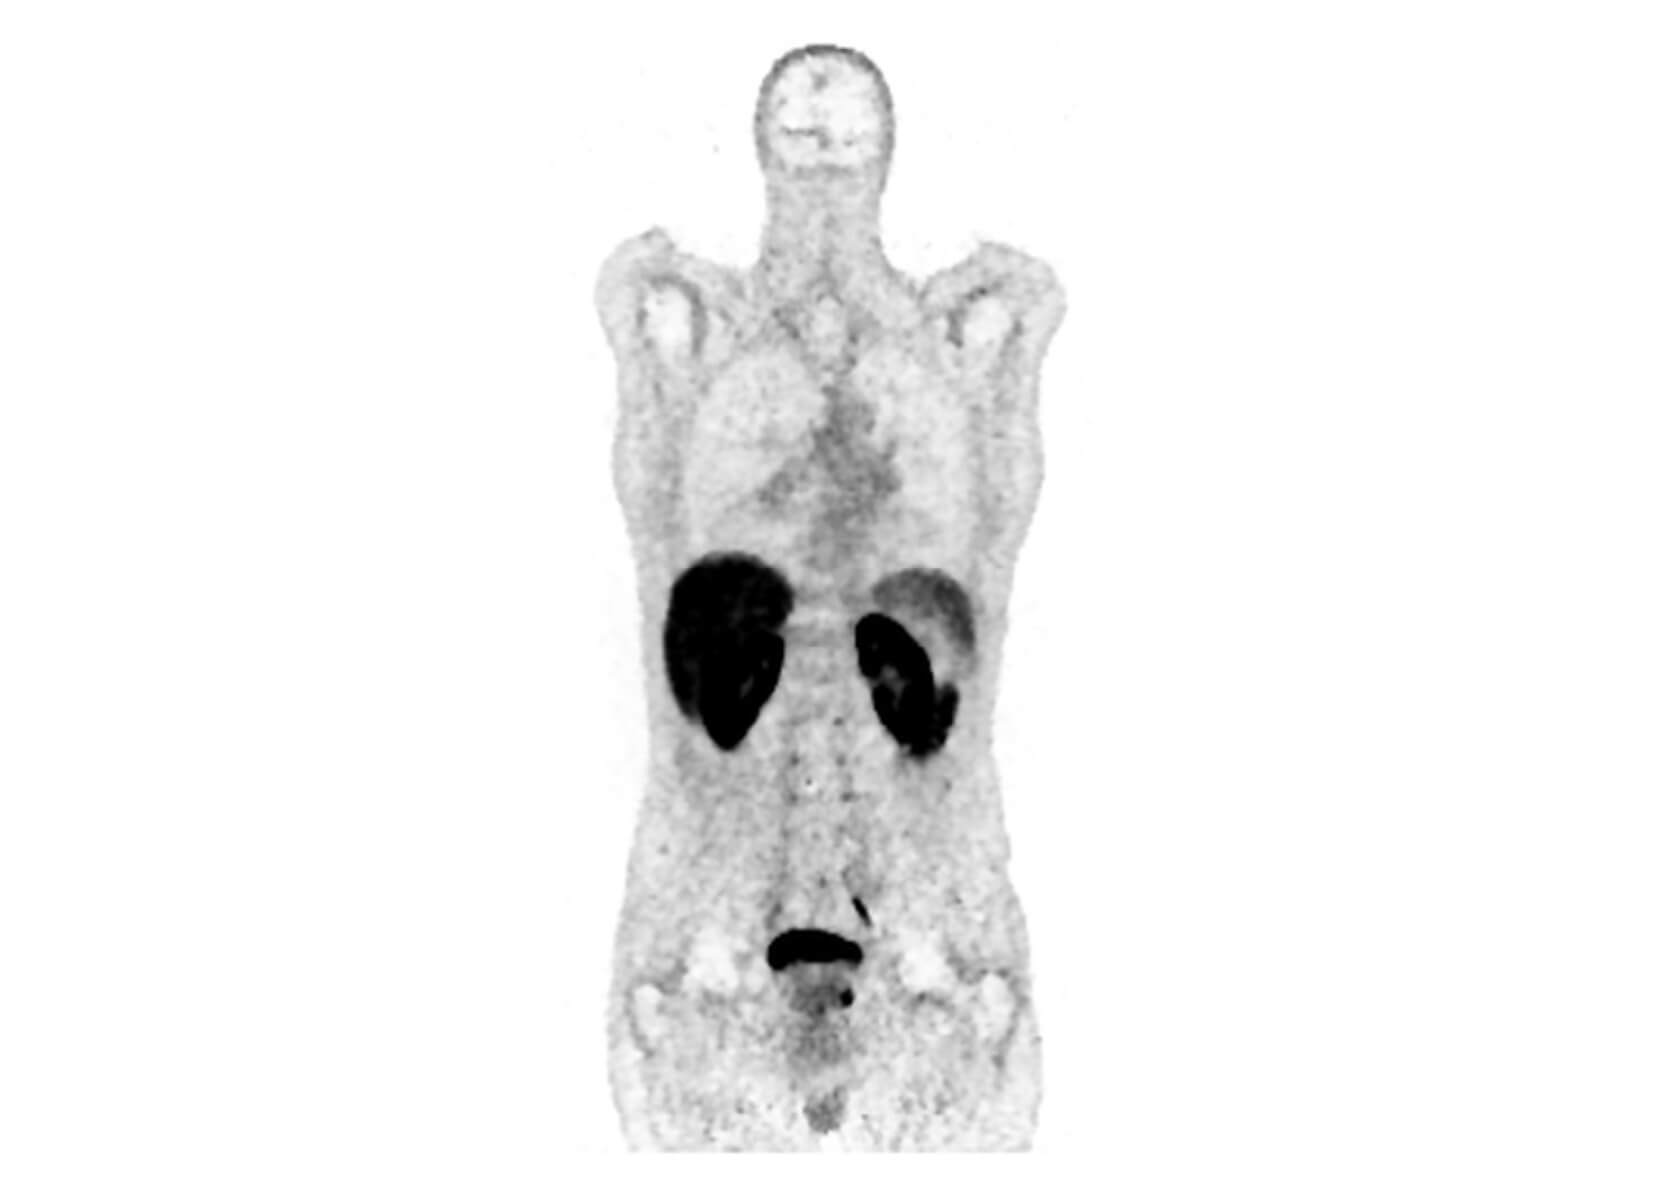

Conventional

ACQ TIME:

20 min

SubtleHD™(PET)

5 min

18F-Florbetapir (AMYLOID)

Philips Vereos PET/CT